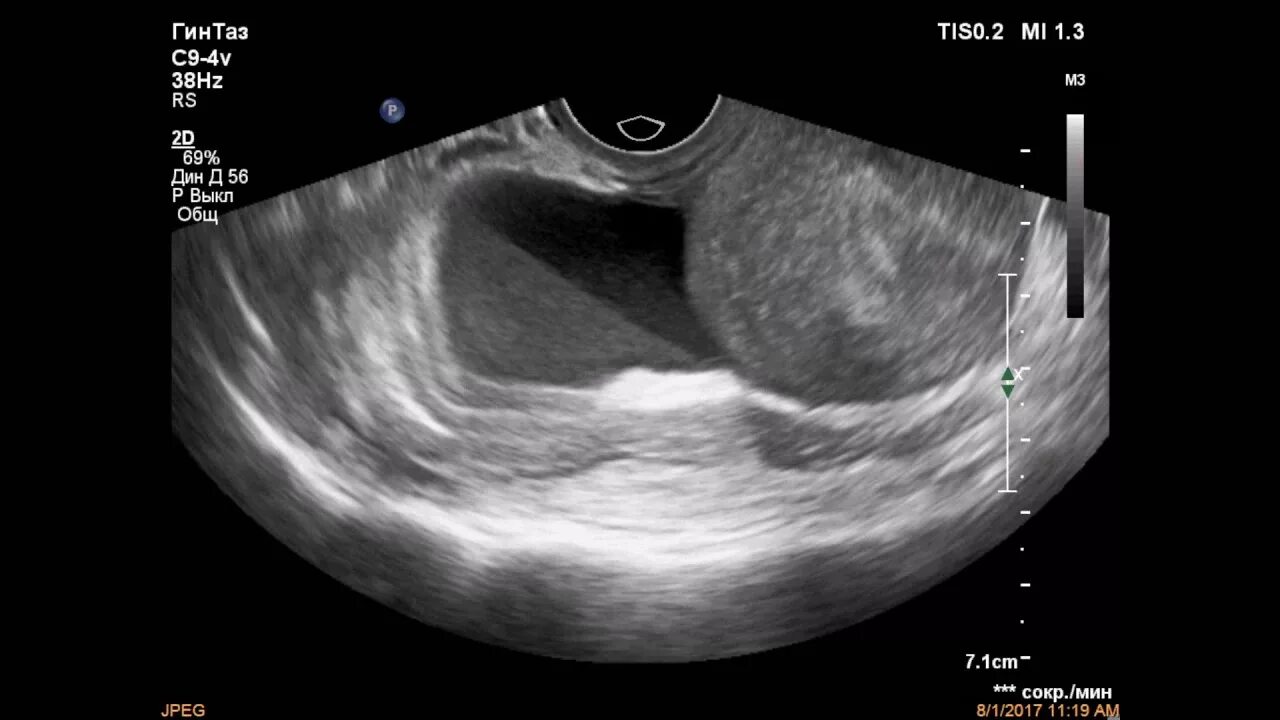

Аппендицит на узи можно ли